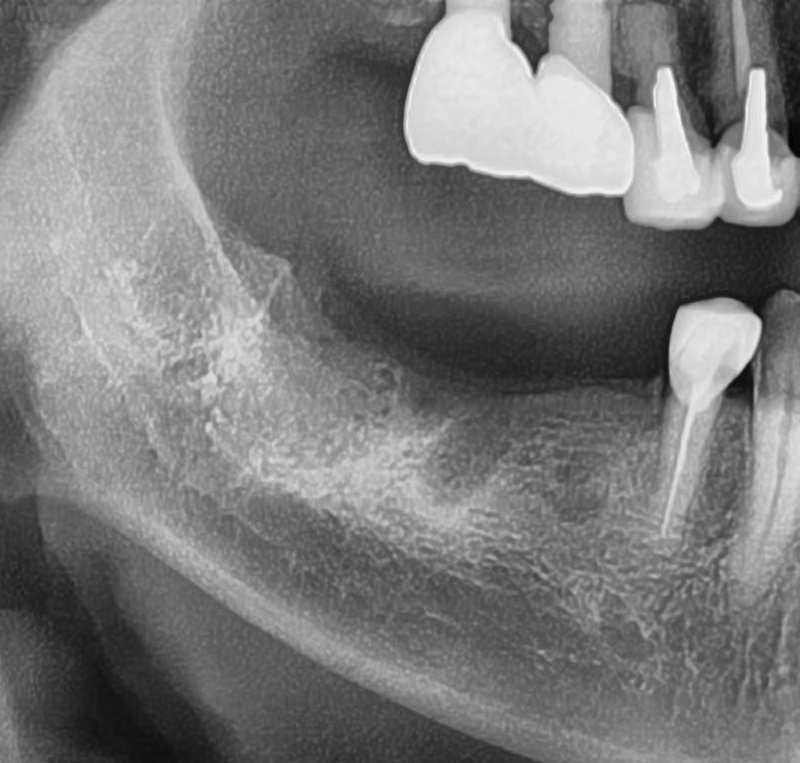

今回の患者様はインプラント植立を希望され、右下5番目・6番目・7番目の合計3本植立が決まりました。

しっかりとインプラント埋め込まれた後は、動揺がないか、噛んだ時に当たらないかなどを確認して、最後にパノラマ写真を撮影して今回のオペは終了となりました。